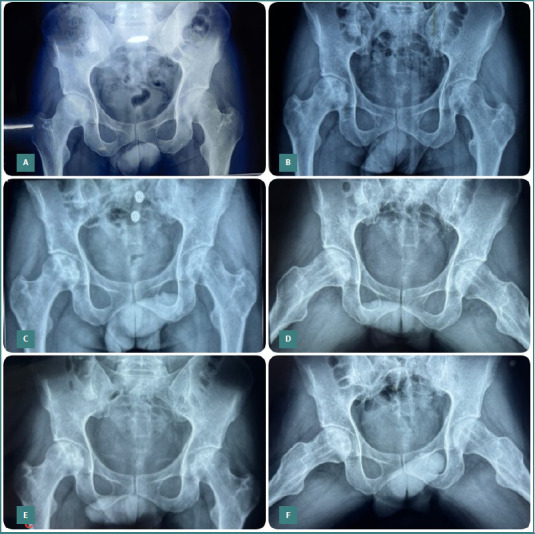

Osteonecrosis of the femoral head (ONFH) is a challenging condition that mainly affects young and middle-aged adults, causing pain, disability, and joint collapse. Current treatment options include medications, physical therapy, and surgical interventions such as core decompression and total hip replacement. However, there is growing interest in regenerative medicine for managing ONFH. This study evaluated the outcomes of core decompression augmented with adult autologous live cultured osteoblasts (AALCO) in patients with early-stage ONFH. Patients diagnosed with ONFH, Ficat-Arlet Grades 1, 2, and 3, underwent a staged procedure involving bone marrow aspiration and the cultivation of 48 million osteoblastic lineage cells. Subsequently, this culture was injected following core decompression and curettage of the necrotic area in the femoral heads. Patients were then followed for 18 to 26 months and evaluated for radiological progression of the disease and changes in functional outcome using the Harris Hip Score (HHS) and Visual Analog Scale (VAS). Forty-eight hips (34 patients with 14 bilateral ONFH) were included in the study and followed up for 18 to 26 months. During this period, 29 patients (40 hips) exhibited progressive signs of healing, resulting in a significant improvement in the mean HHS and a reduction in VAS scores. Core decompression augmented with implantation of autologous live cultured osteoblasts is a reliable treatment approach for managing the early stages of ONFH in young patients caused by various factors. The method aims to halt disease progression through osteoblastic stem cell-mediated new bone formation, leading to improved functional outcomes and potentially delaying or avoiding the need for total hip arthroplasty.